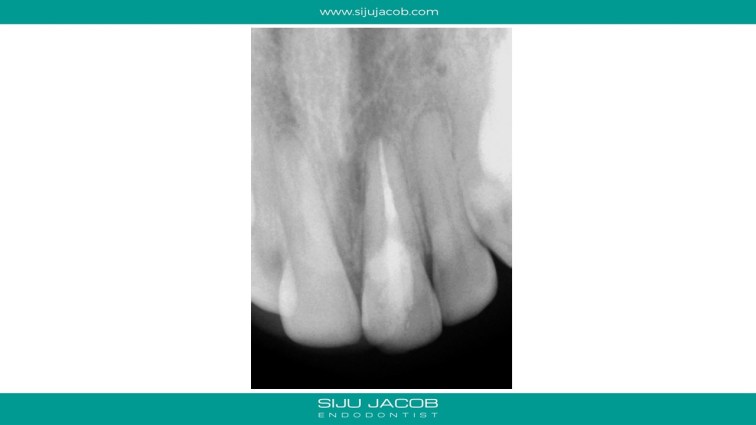

The internal resorption in this case was quite aggressive, but not perforating externally. It is always fascinating to see how much of tooth destruction happens in these cases. Even after cleaning up the soft tooth structure, the underlying hard dentine keeps flaking away and continues to have “bleeding points”. Munce burs are quite useful in cleaning up the altered dentine. By the time I cleaned up till there were no more “bleeding points”, there wasn’t much tooth structure left coronally. I put a fiber post to give some strength coronally. I treated this case before I was aware of Trichloro acetic acid (TCA).